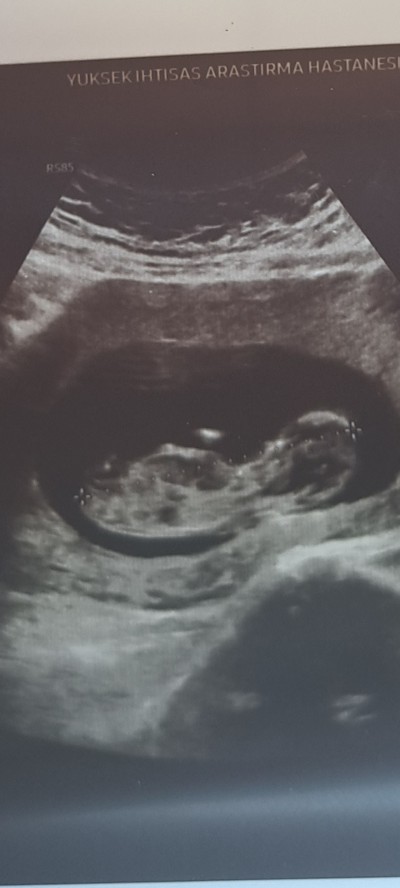

Merhaba arkadaşlar 12+1 gebeyim ultrason görüntüsünden cinsiyet tahmini yapmaya çalışıyorum acaba yardımcı olur

musunuz

Gebelik haftası 12

Kesinlikle kiz gibi görünüyor erkeklerde yukarı doğru olur çünkü kızlarda assagi doğru veya düz gözükür büyük ihtimalle kiz hayırlısıyla gelsin inşallah

Senin bebegim% 100 erkek

Bence kiz 2 kızım var şimdi 21 haftalık erkek bebeğe gebeyim ayni kızlarımın  ultrason şekline benziyor

Bence erkek içimden geçti hayırlısı olsun

Kız canım kız <3